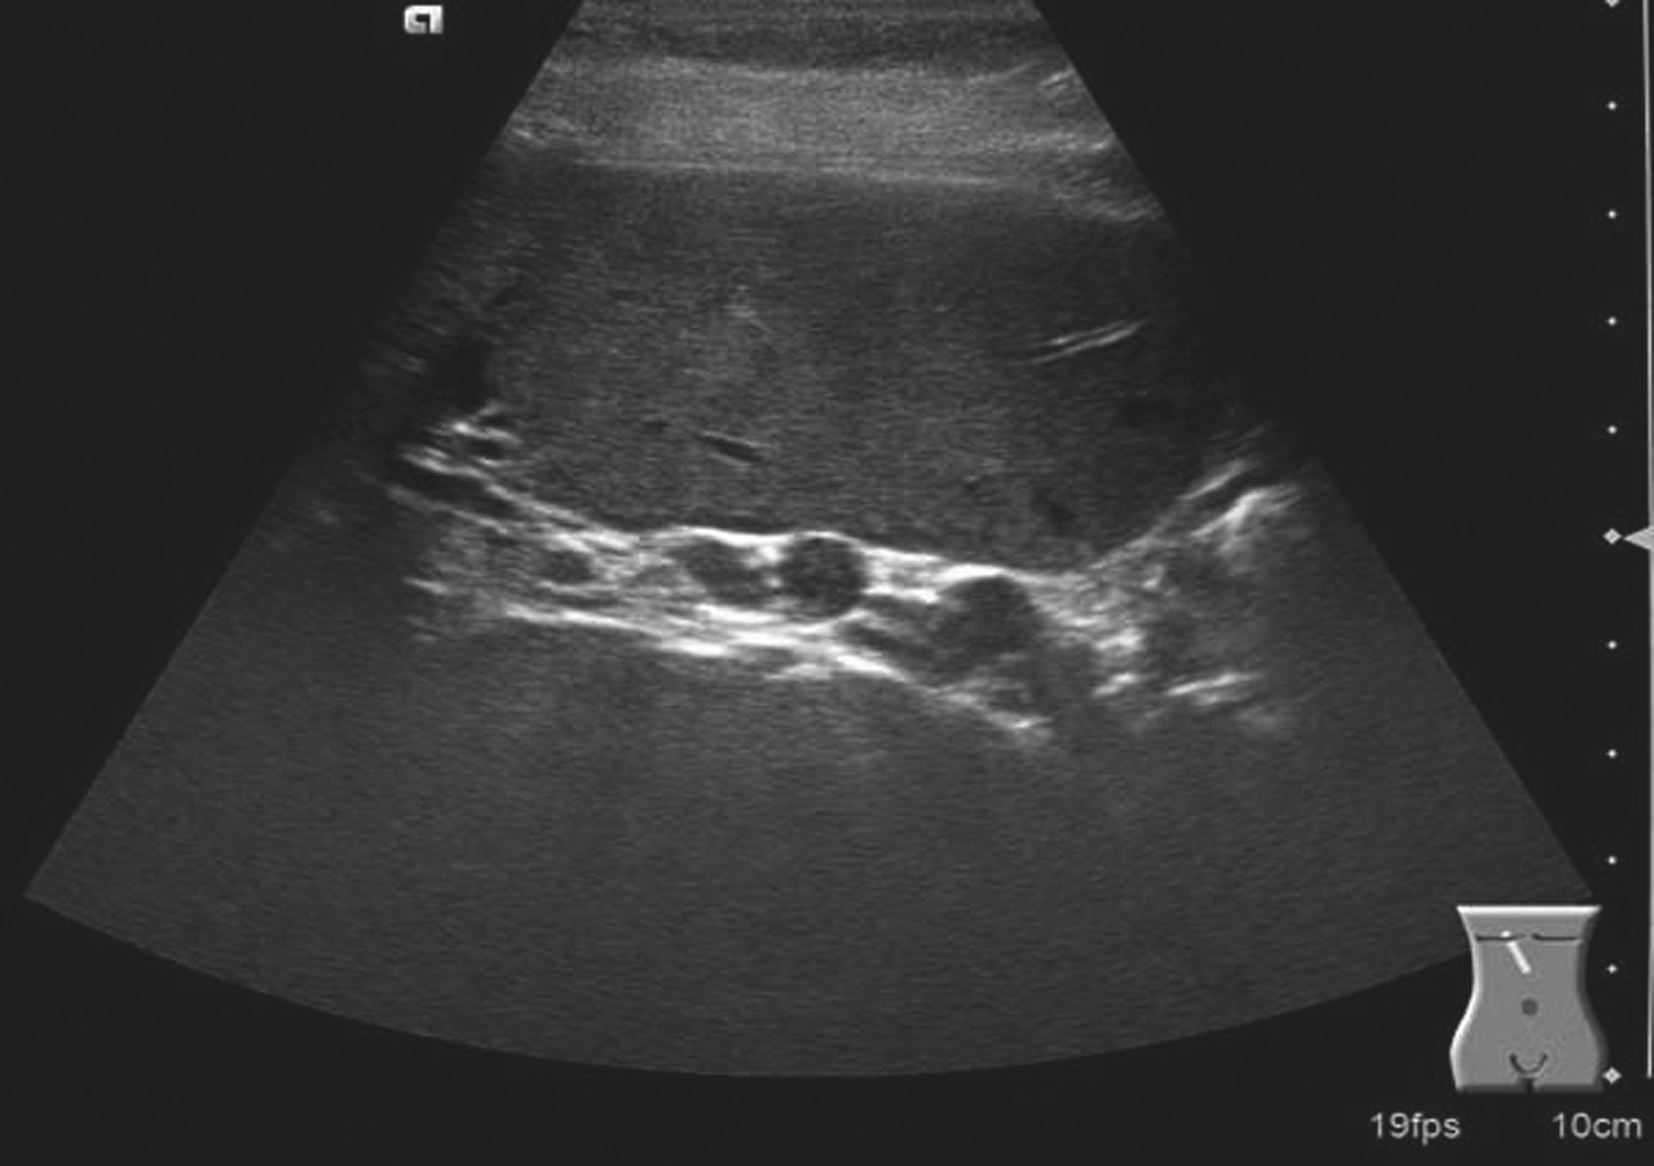

【声像图表现】

(1)灰阶超声:

肝门区结构紊乱,肝外门静脉周围或管腔内可见多条弯曲成团的血管,呈蜂窝状或网格状无回声区结构,在结构紊乱的肝门部仔细辨认可见管腔狭窄、壁增厚回声增强的门静脉管道,管腔内可见癌栓或血栓,部分可压迫胆道系统造成肝内外胆管扩张。可出现继发门静脉高压声像图改变,如脾肿大、脾静脉及肠系膜上静脉增宽,严重者可见腹水。

(2)彩色多普勒血流显像:

在肝门区蜂窝状或网格状无回声区结构内充满色彩暗淡的彩色血流信号;门静脉狭窄者于门静脉内探及少许连续性彩色血流通过,其周围蜂窝状液性无回声区呈红、蓝相间的不连续彩色血流信号;完全闭塞或栓子充填的门静脉内则无彩色血流信号显示;如图5-21-26所示。

(3)频谱多普勒表现:

门静脉海绵样变性区域于蜂窝状或迂曲的管状无回声区内均可探及门静脉样连续状低速血流频谱;如图5-21-27所示。

图5-21-26 门静脉海绵样变性二维灰阶图像

图5-21-27 门静脉海绵样变性彩色多普勒图像